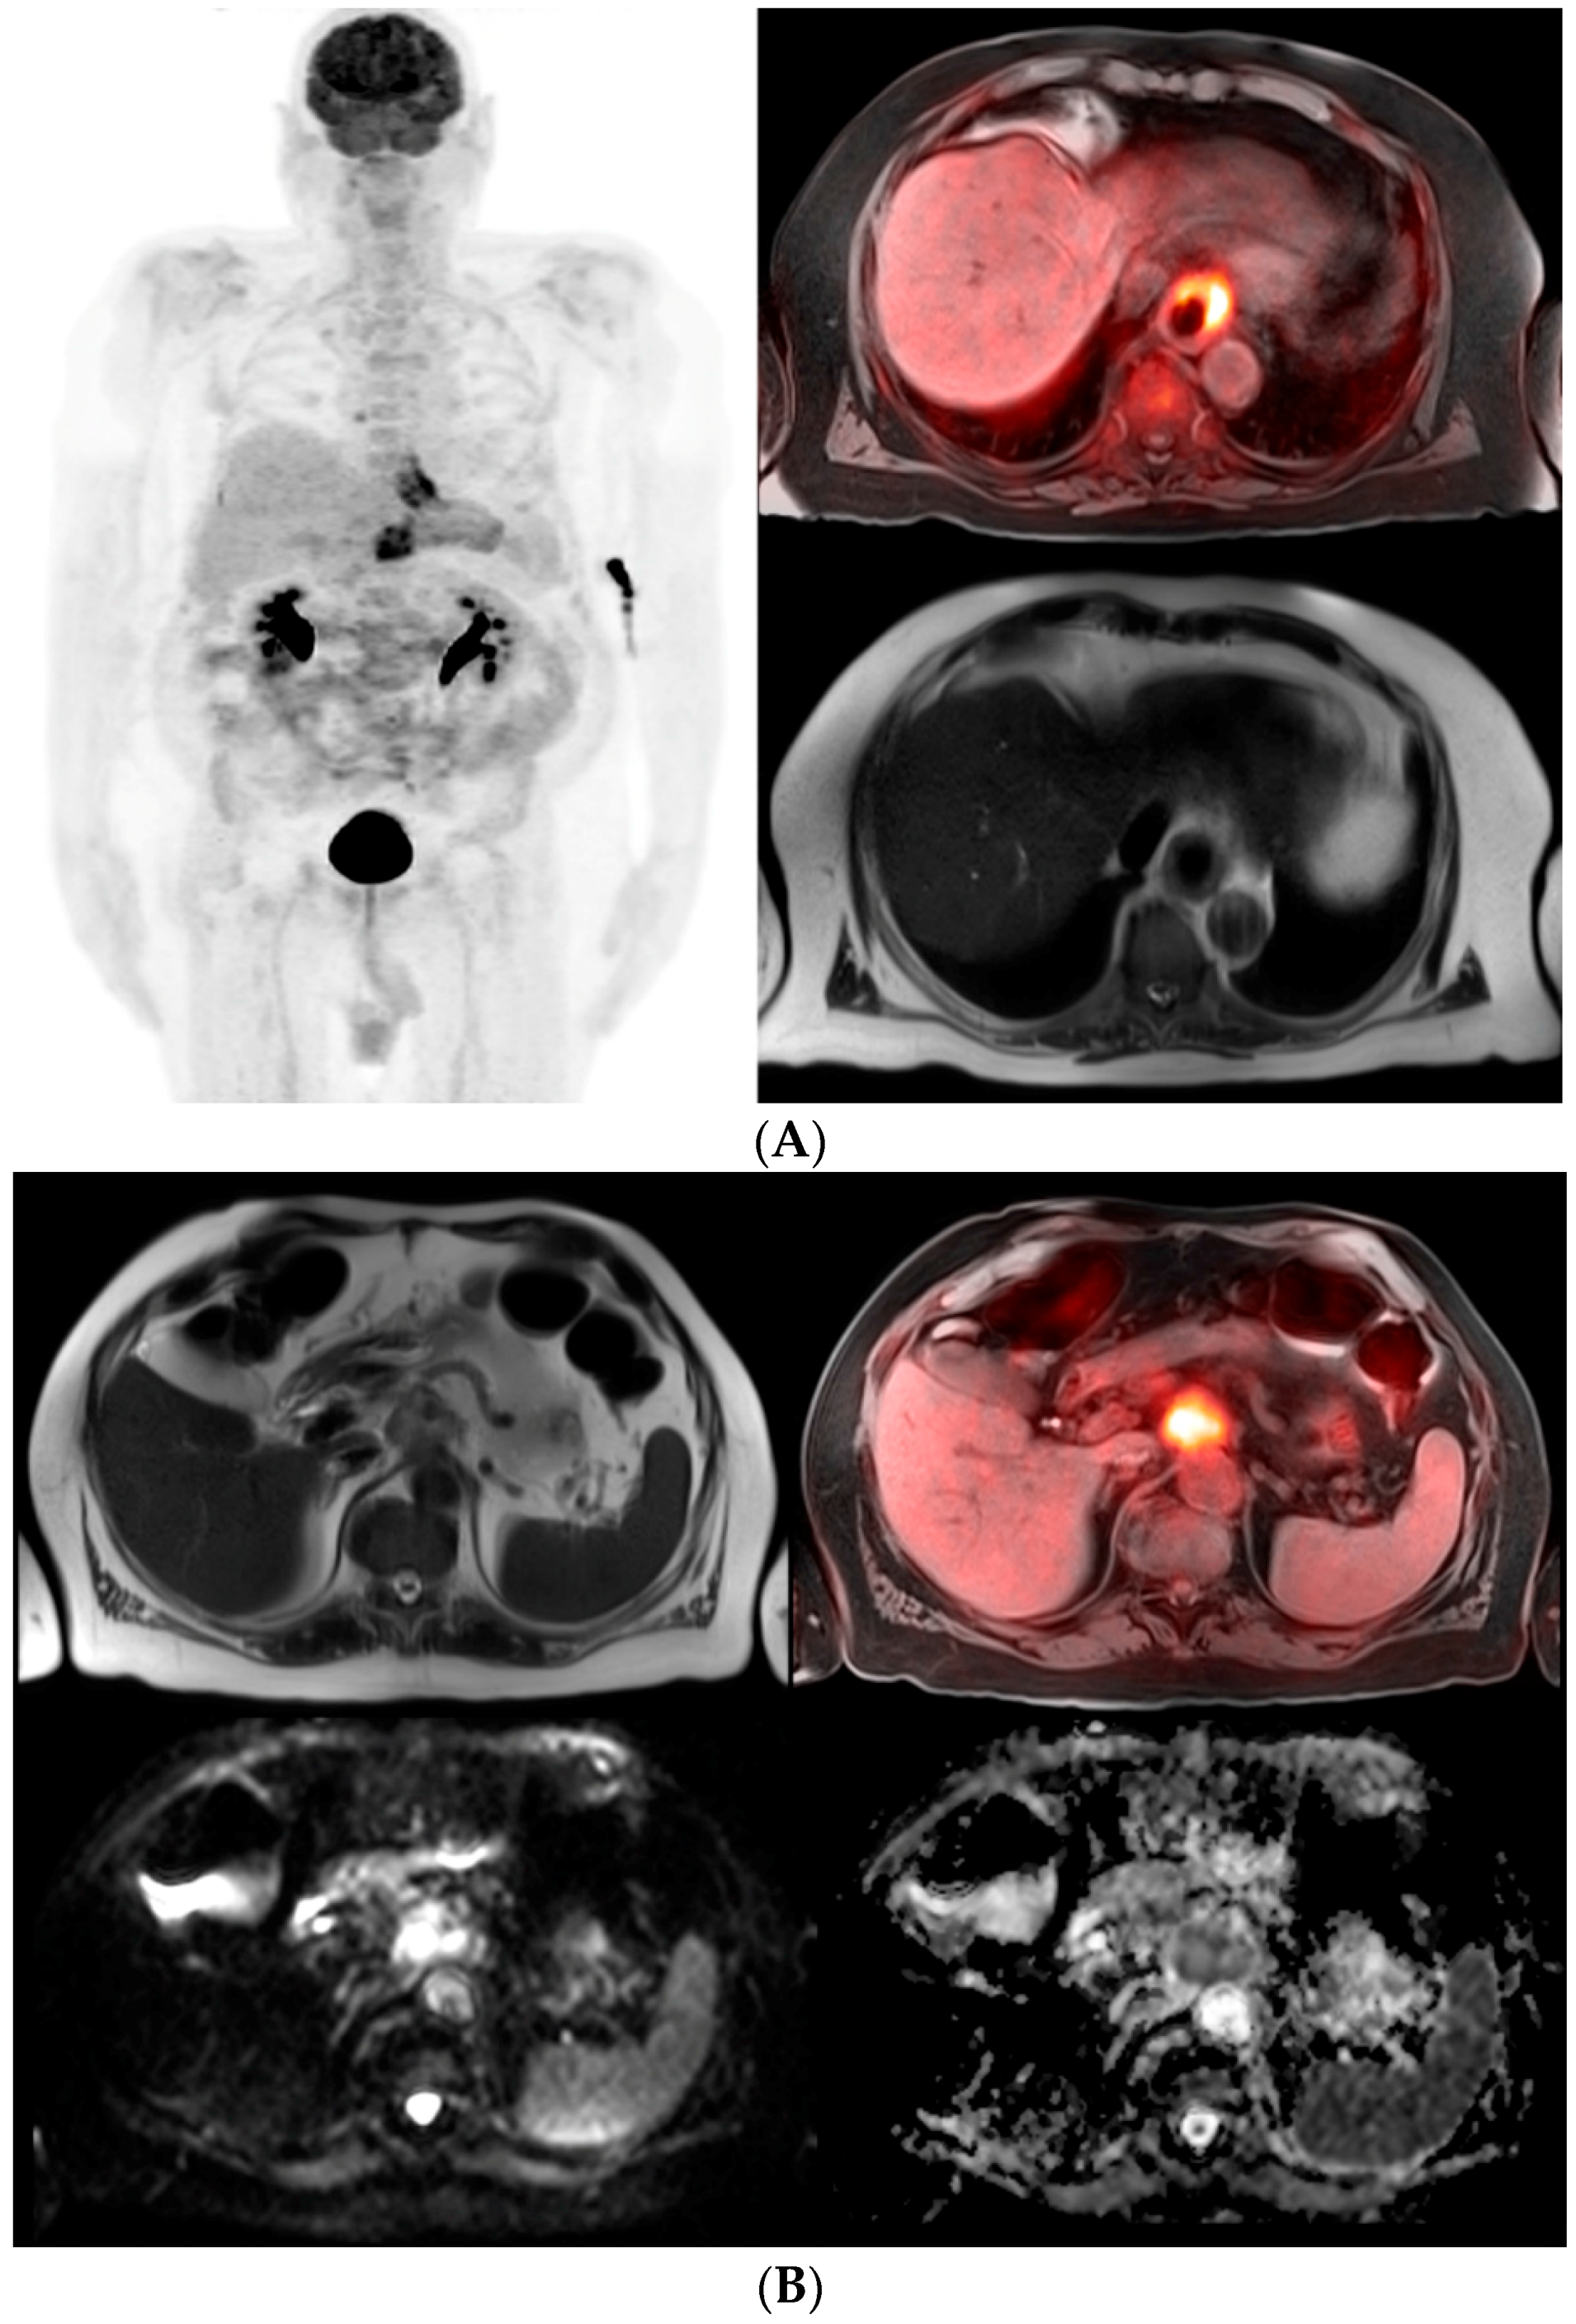

The rapid evolving PET-MRI imaging modality with its superior soft tissue resolution and metabolic activity has potential in initial staging of esophageal cancer. With the improvement of MRI cameras, protocols, and techniques that resulted in high quality imaging, staging of esophageal cancer has significantly improved. Diffusion weighted imaging with the conjunction of high resolution T2 weighted MRI images, the extent of tumor wall invasion as well as local and distant metastases have improved. Other sequences like STIR and TSE have also improved diagnostic accuracy. MRI contrast agents may even detect small lesions which are difficult to see [17,18]. Various MRI imaging protocols for esophageal cancer have been established. In one small series of 19 patients, PET/MRI imaging demonstrated comparable accuracy for T staging (80%–86%) with EUS and higher accuracy for N staging (83% sensitivity) compared to both EUS and PET-CT (75%–67%). In addition, PET-MRI was able to detect distant metastatic disease as shown in Figure 1 [19].

Figure 1.

(A) 71-year-old male with a history of esophageal adenocarcinoma with an esophageal stent. PET maximum intensity projection (MIP) images demonstrate two abnormal FDG foci corresponding to the distal esophageal mass and an upper abdominal metastatic lesion (left image). The fusion PET-MRI transaxial image using T1 with fat suppression shows prominent abnormal FDG uptake in the distal esophageal cancer (top right). The T2 haste transaxial image demonstrates eccentric esophageal wall thickening (bottom right); (B) Metastatic lymph node from esophageal adenocarcinoma. The T2 haste transaxial image shows an enlarged lymph node located superior to the celiac axis of the aorta (top left). Fusion PET-MRI image using T1 with fat suppression reveals prominent abnormal FDG activity consistent with metastasis (top right). Diffusion weighted images demonstrate hyperintense signal in the enlarged lymph node (bottom left) with corresponding low signal on the apparent diffusion coefficient map (bottom right) which is consistent with malignancy.